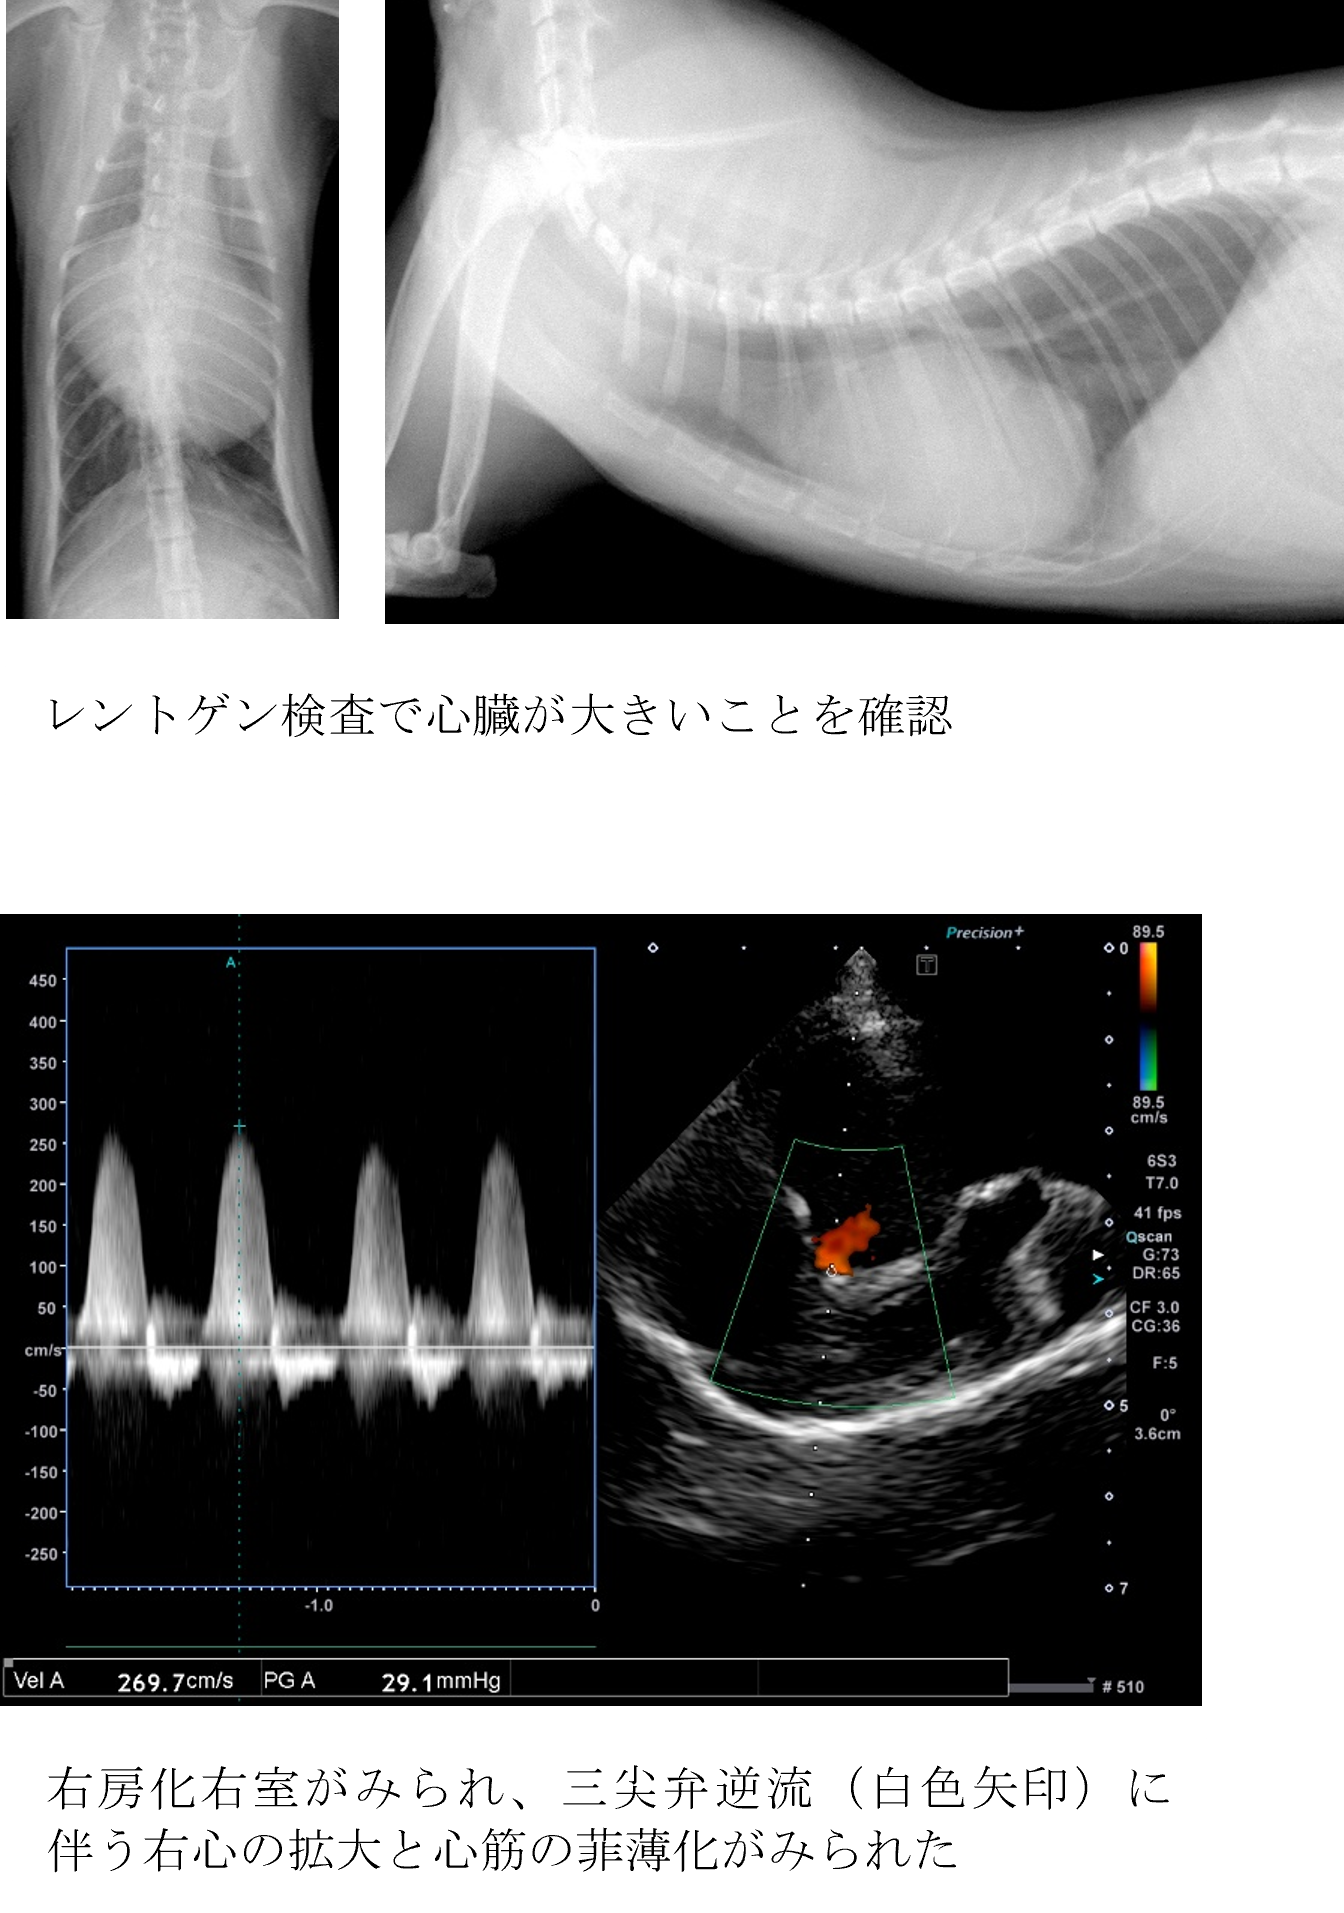

症状は何もなく健康診断で心臓に異常がみられた。

各種検査より、エプスタイン奇形と診断しました。

エプスタイン奇形は、右心房と右心室の間にある三尖弁の弁輪が右心室側にずれてしまうことで、三尖弁の機能や右心室のポンプ機能が低下したり、不整脈を起こしたりする病気です